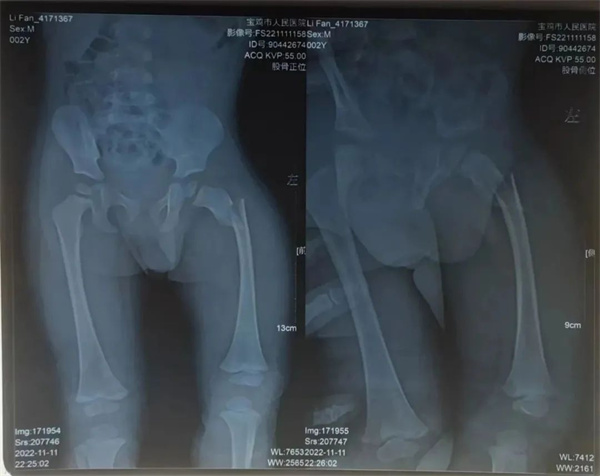

两岁的帆帆因为在家中玩耍时不慎踩空从楼梯上摔落,孩子哭闹不止,父亲发现孩子大腿明显肿胀,遂来市人民医院急诊科就诊。急诊科为其进行X线检查显示 “左股骨粗隆下骨折、断端错位明显”,建议患儿住院行进一步专科治疗,遂患儿转入骨一科。

刚受伤时照片